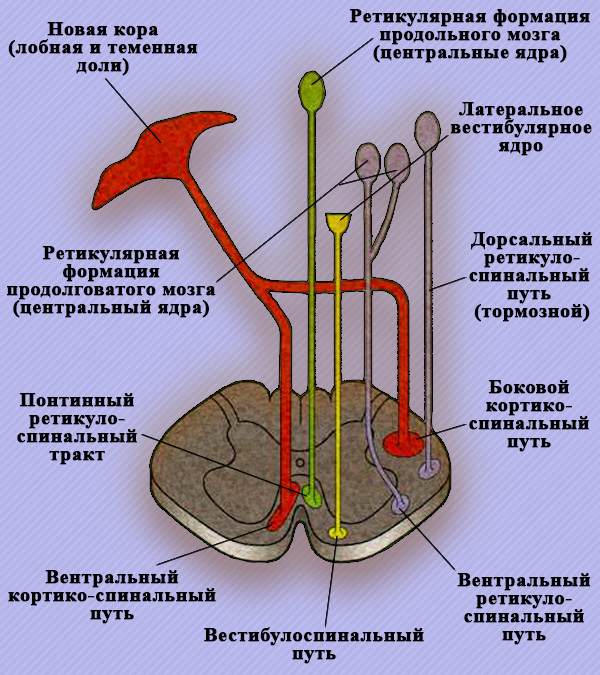

Преддверно-спинномозговой путь пролегает без перекреста от ядра Дейтерса (латерального вестибулярного ядра, которое принадлежит VIII паре черепно-мозговых нервов; см статью «Черепно-Мозговые Нервы. Общие сведения») к клеткам передних рогов спинного мозга. Активирующие и тормозные ретикуло-спинальные тракты начинаются от ствола головного мозга и среднего мозга (рисунок 3).

Рисунок 3. Нисходящие пути спинного мозга

Два из четырех тормозных путей (дорсальный и вентральный ретикулоспинальные пути) являются моноаминергическими (норадреналин, серотонин и дофамин):

Активирующий ретикуло-спинальный тракт начинается от варолиева моста в передних канатиках возле передней срединной щели спинного мозга.

Вестибулярно-спинальный и ретикуло-спинальный пути отвечают за начало двигательной активности. Два моноаминергических тормозных ретикуло-спинальных пути ингибируют поток нервных импульсов (афференты) сгибательных рефлексов. Дорсальный ретикуло-спинномозговой путь угнетает афферентную часть полисинаптической рефлекторной дуги сгибательного рефлекса на сегментарном уровне. Вентральный ретикуло-спинальный путь ингибирует моносинаптическую часть дуги с участием разгибателей, таким образом облегчая тонкие координальные движения. В случае повреждения этих трактов повышается тонус мускулатуры и активируются рефлекторные реакции.

Активирующие волокна ретикуло-спинального пути обеспечивают антигравитационный тонус человека в положении стоя. При активации этого тракта активирует тонус мышц-разгибателей нижних конечностей и мышц-сгибателей верхних конечностей. Аналогичную функцию выполняет и вестибуло-спинномозговой тракт. В мозжечке образуются нервные импульсы, которые направляются в основном к латеральному вестибулярному ядру, затем поступают в его нисходящий тракт.